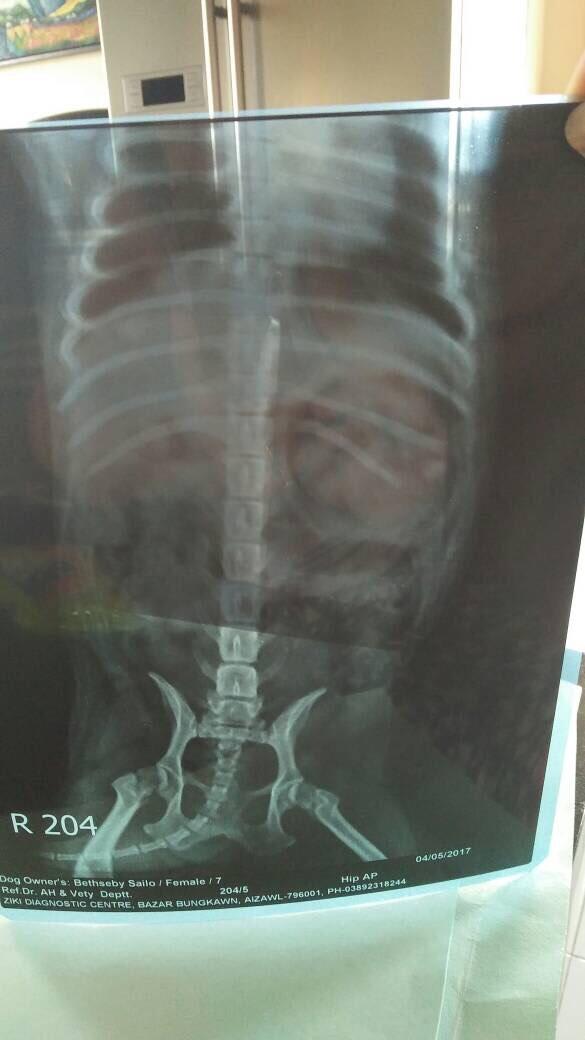

Pet's info: Dog | Pug | Female | unspayed | 7 years old | 19.8 lbs

My pug (F,6yr old) is unlable to walk due to her hind limb.She started limping a little bit since Sepember 2016 and it got worse as she could climb up on the bed or stairs, so this year march, we did an xray, right after which she stopped walking. She could not walk, and one vet says she has hip dysplasia and the other vet says it may be disc prolapse. I dont know what to believe as in a small town like ours, we cannot do ct scan nor mri for dogs hence its very difficult to diagnose.Pls help

I would recommend referral to an orthopedic or neurology specialist in order to correctly determine the underlying cause and to establish a management program going forward to maintain her mobility in the future; the longer this goes untreated the greater chance of permanent changes that may not respond to treatment. Weight management, antiinflammatory medications and diets specifically formulated for joint health and mobility (royal canin mobility / hills joint care) are recommended and acupuncture or chiropractic care may also help with the symptoms